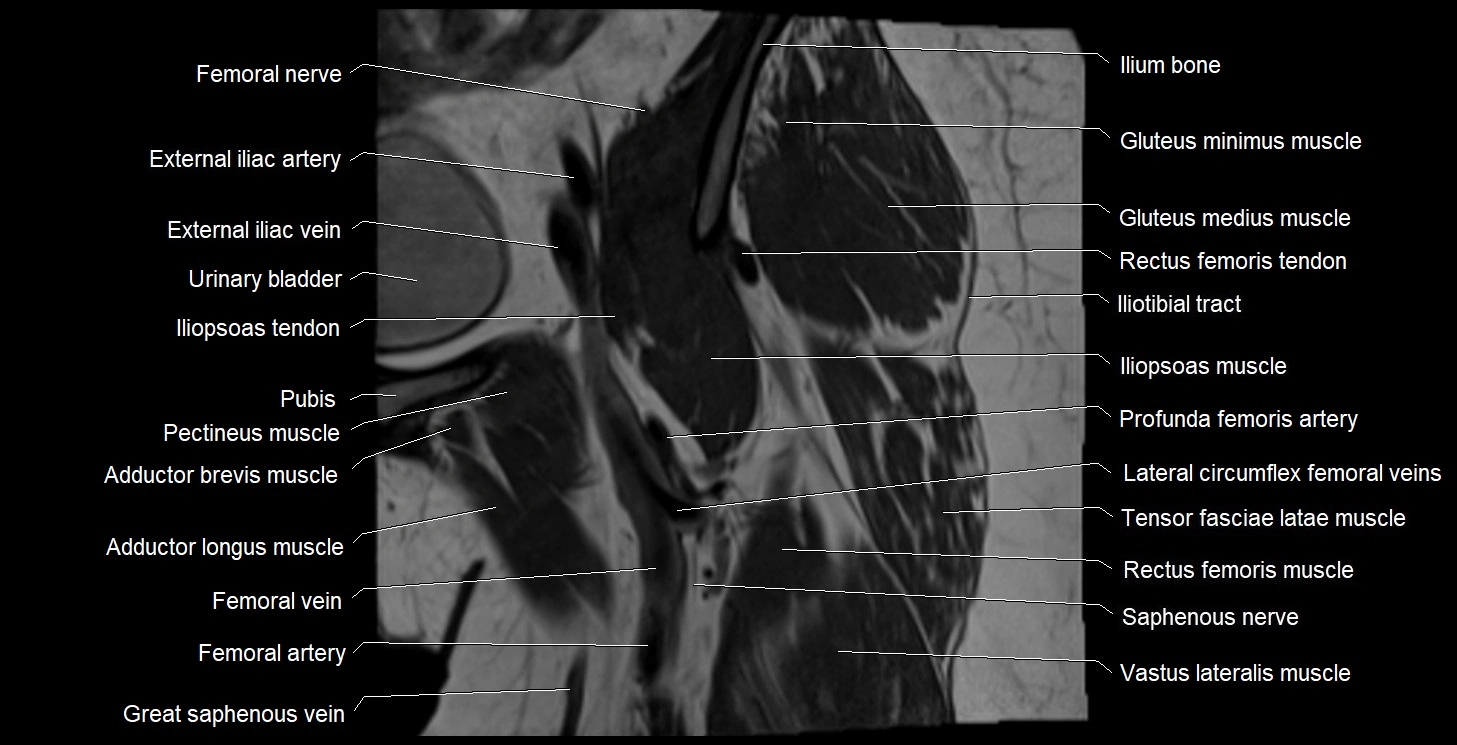

- External iliac artery

- External iliac vein

- Femoral artery

- Femoral nerve

- Femoral vein

- Gluteus medius muscle

- Gluteus minimus muscle

- Iliopsoas muscle

- Iliopsoas tendon

- Iliotibial tract

- Ilium bone

- Lateral circumflex femoral veins

- Pectineus muscle

- Rectus femoris muscle

- Rectus femoris tendon (Proximal tendon of rectus femoris)

- Saphenous nerve

- Tensor fasciae latae muscle

- Urinary bladder